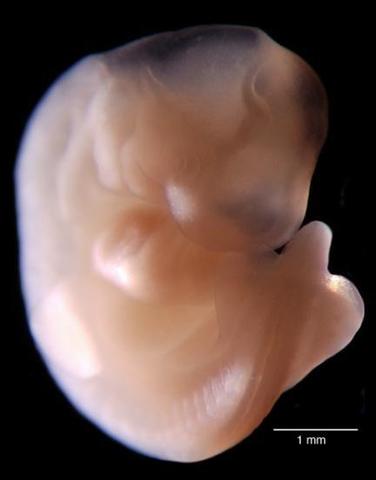

• cuarta semana

cuarta semana

El embrión empieza a desarrollar los vestigios de los futuros órganos y aparatos.El cambio más importante que se produce es el plegamiento del disco embrionario: la notocorda es el diámetro axial de un disco que comienza a cerrarse sobre sí mismo, dando lugar a una estructura tridimensional seudocilíndrica que empieza a adoptar la forma de un organismo vertebrado